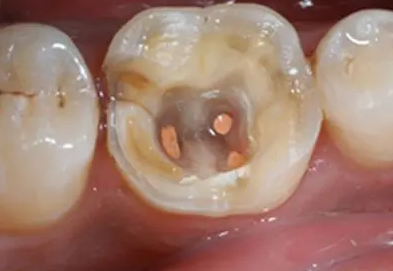

当蛀牙才刚刚萌发的时候进行治疗,只需要简单补牙就可以解决了;但当蛀牙侵害到牙髓和神经,就不得不根管治疗了。

一般医生会给你局部麻醉,清除根部坏死的牙髓,抽出牙神经后就不会那么痛,但有些牙齿根部长得歪,这时抽神经的难度较大,所以麻醉过程中效果不是很好,而插根管的数量得看牙齿具体位置,前面的牙齿1~2根,像大牙这种就得3~4根,插得越多难度就会增加。